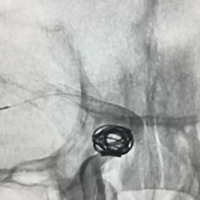

完全释放支架后即刻造影,可见支架贴壁良好。

末次DSA造影见颈内动脉及各分支充盈完整,CT未见脑梗或出血征象。